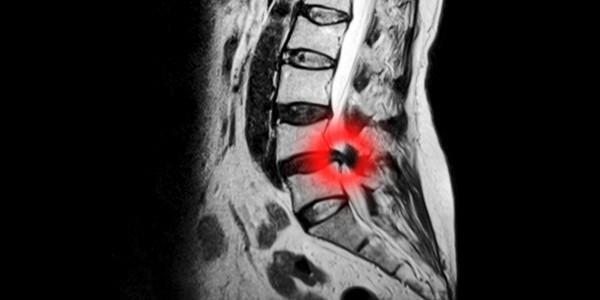

Damage to the disc tissue between each vertebrae can cause it to change shape.  This can be a mild bulging or a herniation of disc tissue, causing it to press on the spinal canal and /or nerves, causing Stenosis.

By decompressing (taking pressure off) a segment of your spine affected by stenosis and stretching the soft tissues, mobility in the spine can be improved.

This can relieve pain caused by muscle spasm, and alleviate nerve compression and irritation caused by herniated or prolapsed discs, that lead to spinal stenosis.